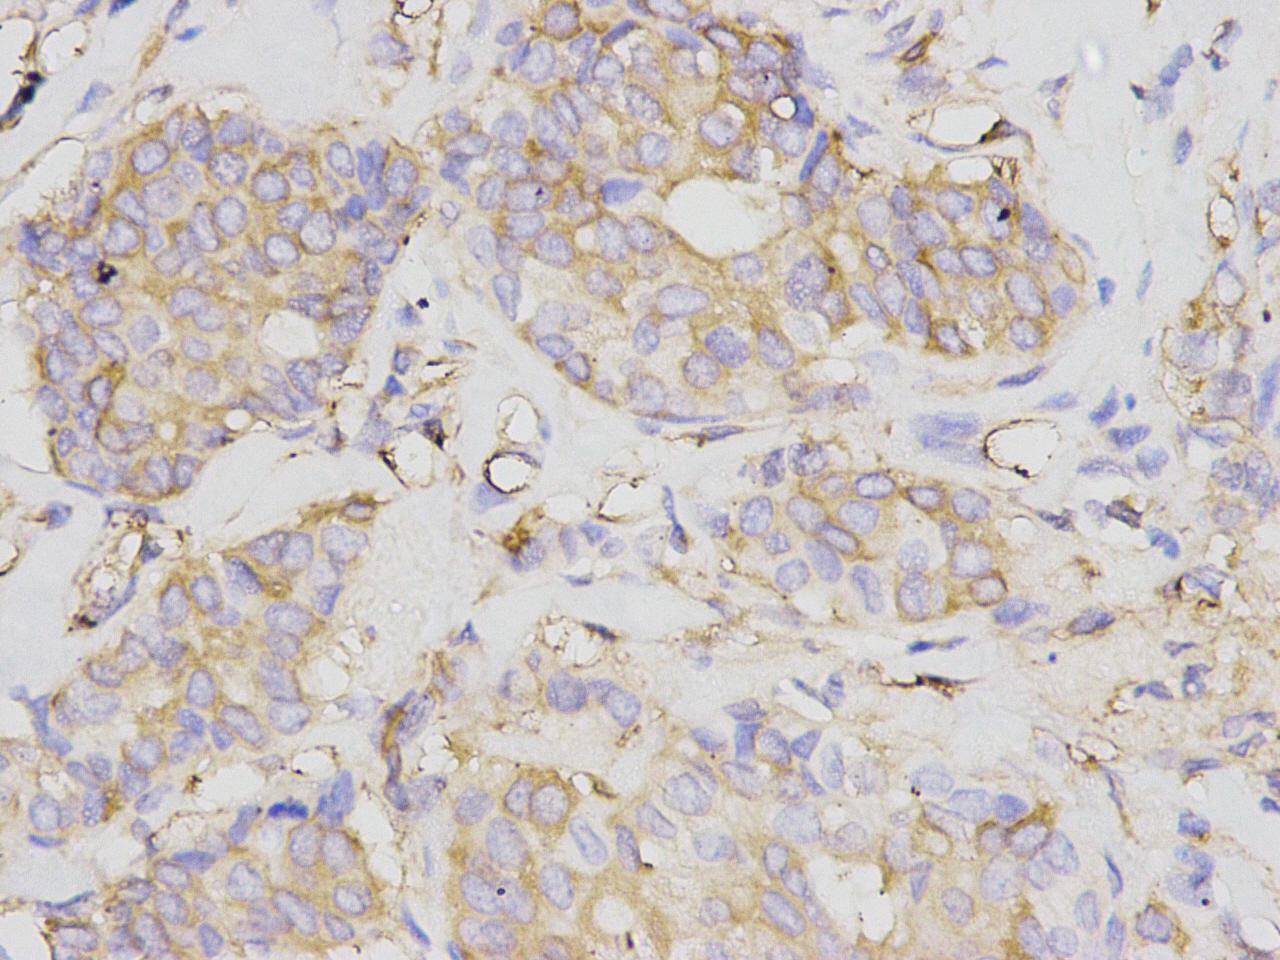

NF-kB p105 / p50 Rabbit Polyclonal Antibody

IHC-P